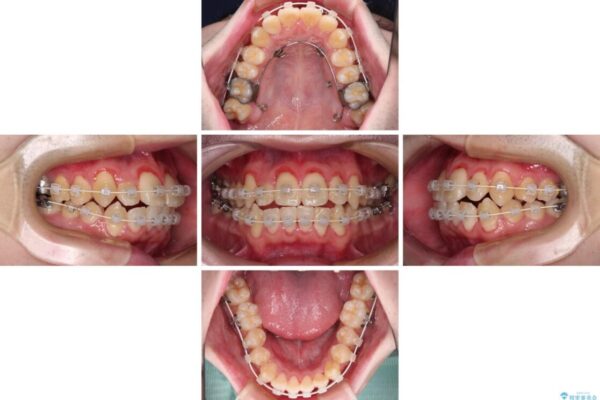

治療途中

• 全顎的なクロスバイト 補助装置を用いてワイヤー矯正 治療途中画像